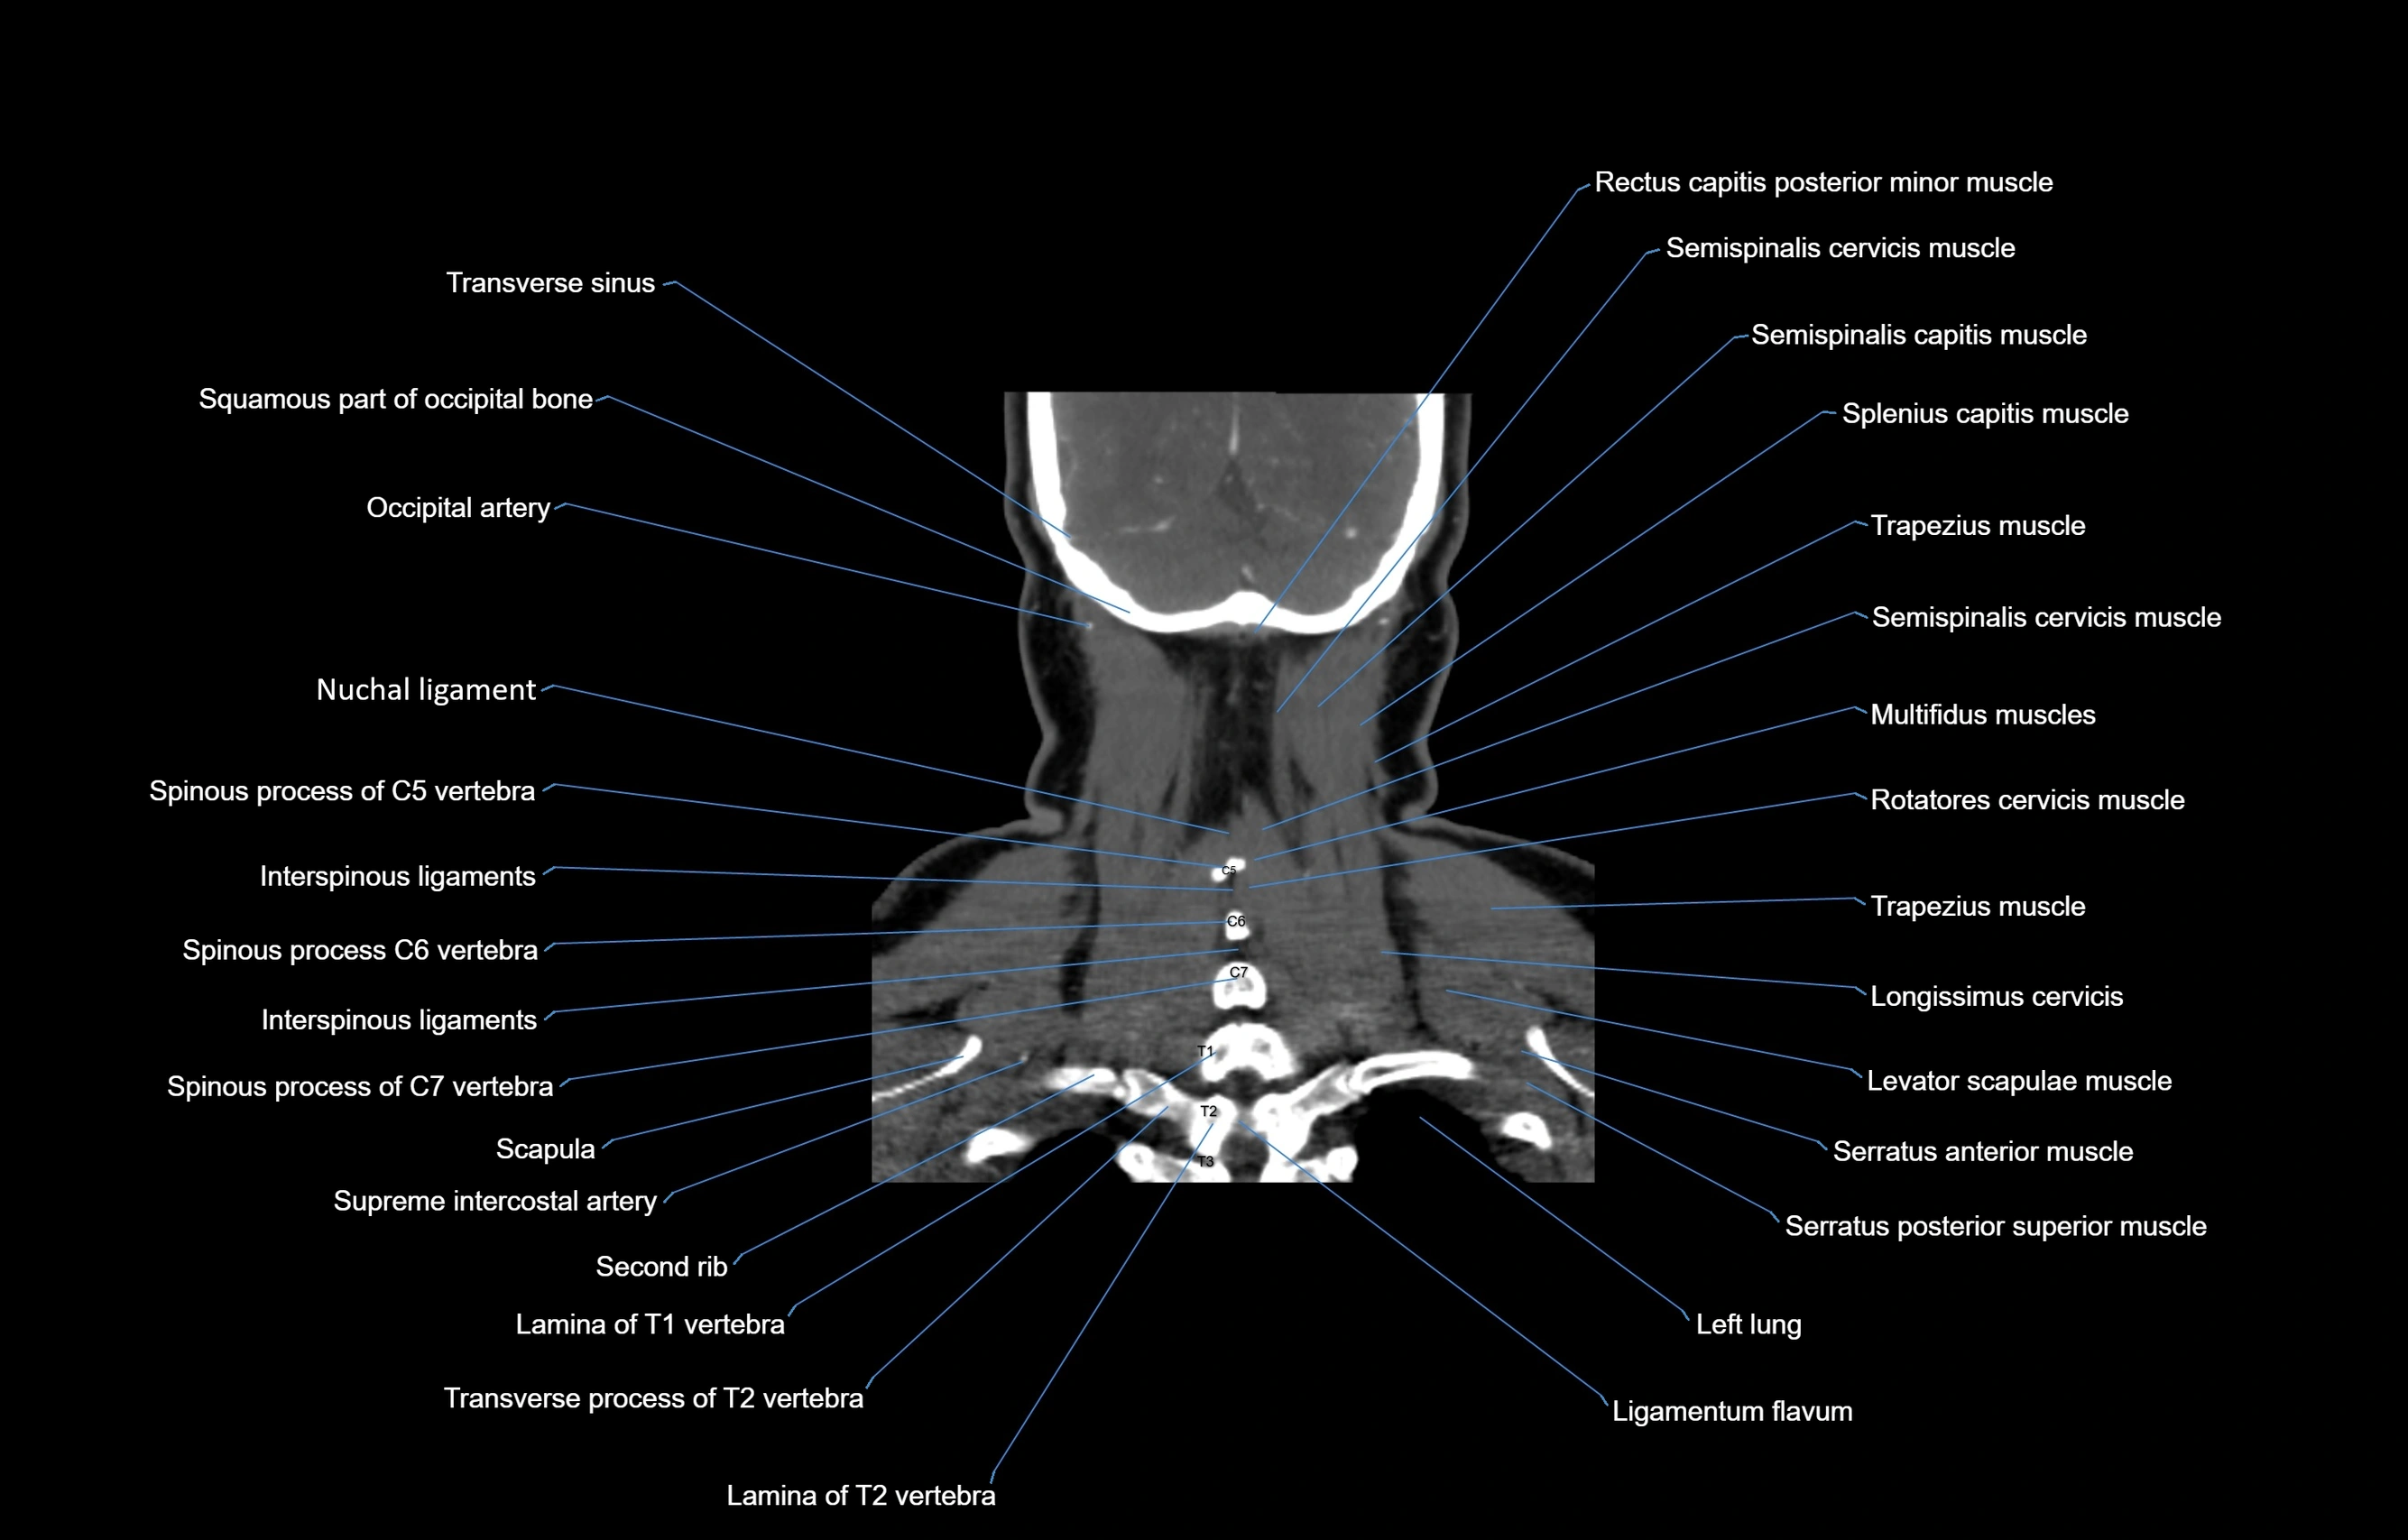

- Interspinous ligament

- Lamina of vertebra

- Ligamenta flava (Ligamentum flavum)

- Longissimus cervicis muscle

- Multifidus muscles

- Nuchal ligament

- Rotatores cervicis muscle

- Rotatores cervicis muscles

- Semispinalis capitis muscle

- Semispinalis cervicis muscle

- Serratus posterior superior muscle

- Spinal cord

- Splenius capitis muscle

- Splenius cervicis muscle

- Trapezius muscle